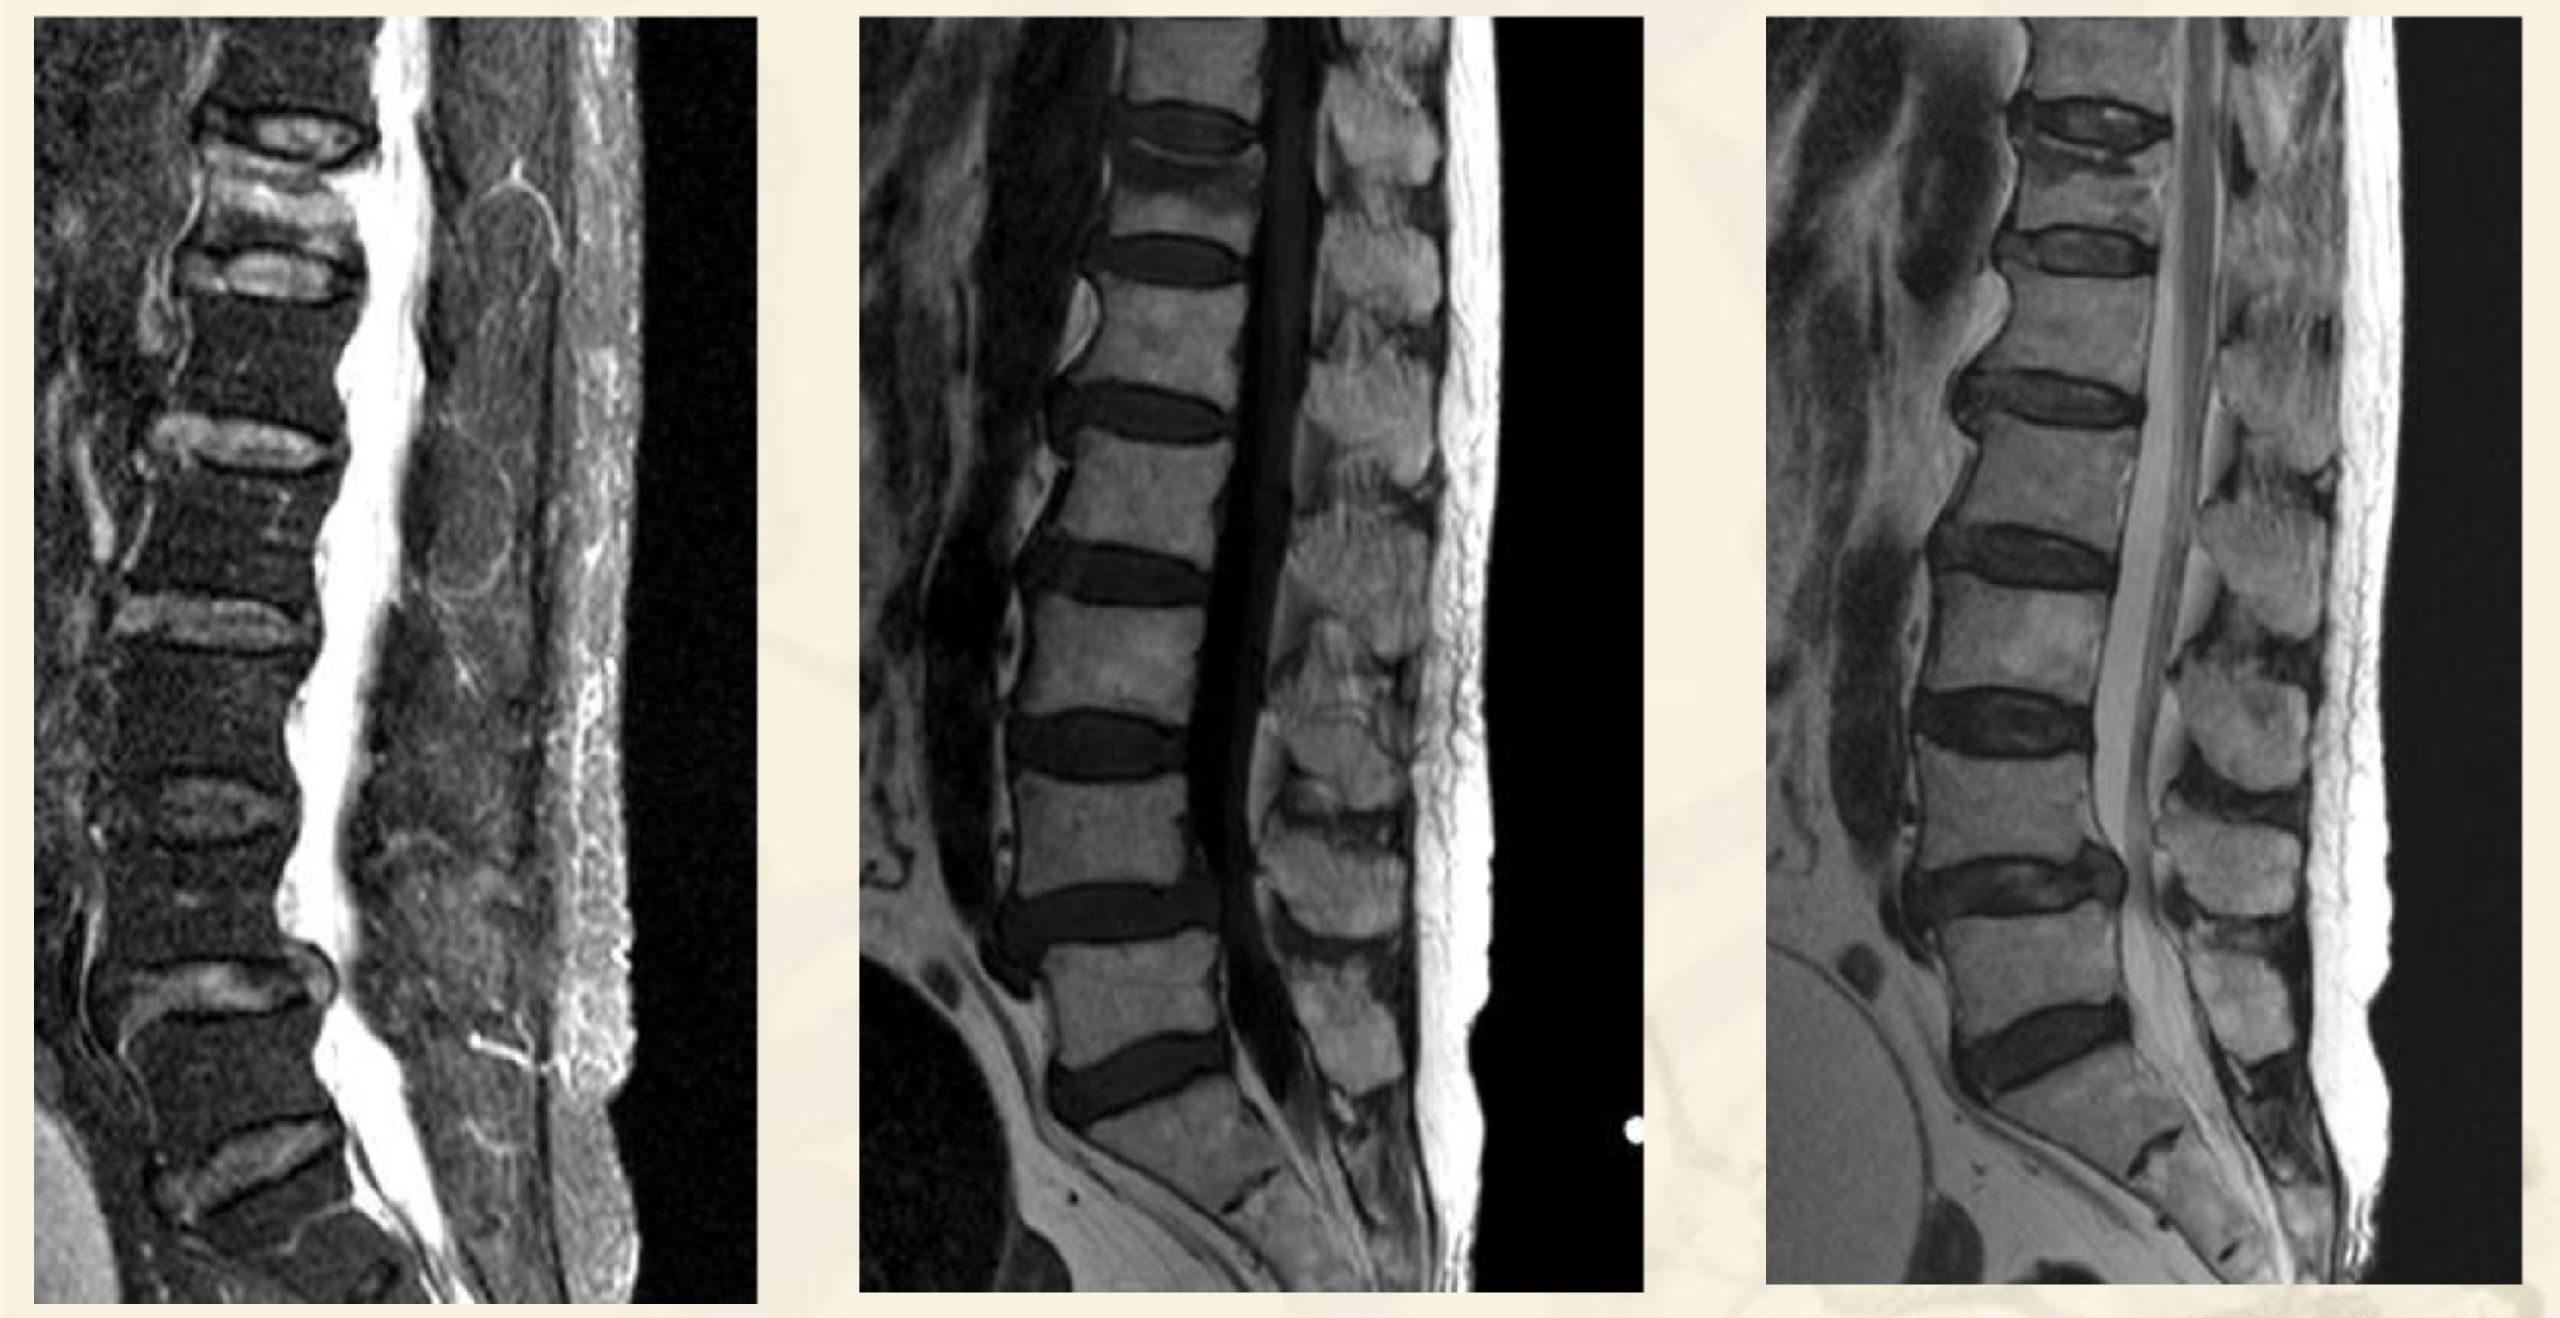

术前X线

术前MRI

术前CT

术中透视图

透视引导下,经椎弓根入路或根旁

靶向骨折区置管

术后X线

术后CT